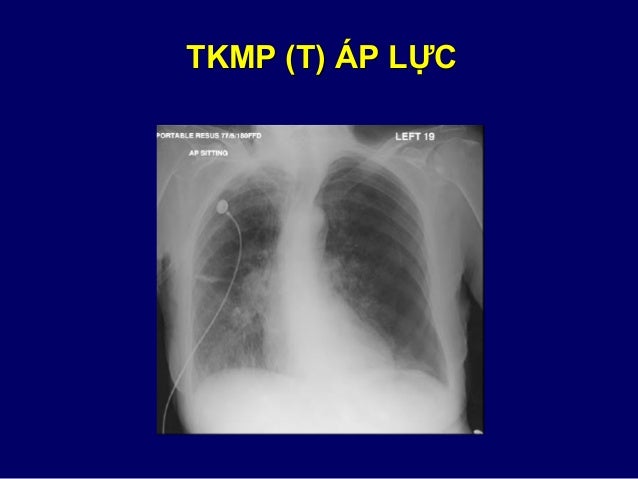

51. 51. TKMP (T) ÁP LỰC

52. 52. TKMP (P)   TƯỚI MÁU PHỔI (T)

53. 53. THÔNG ĐIỆP CẦN NHỚ VỀ TỔN THƯƠNG TRÀN KHÍ  Tìm dấu mất nhu mô + lá tạng màng phổi  Tìm có dấu TKMP áp lực  Phim XQ thì thở ra giúp thấy rõ TKMP nhỏ  Cần phân biệt với nếp gấp da, bóng khí  Hễ thấy gãy xương sườn thì tìm TKMP  TKMP lượng lớn có thể  tăng tưới máu phổi còn lại